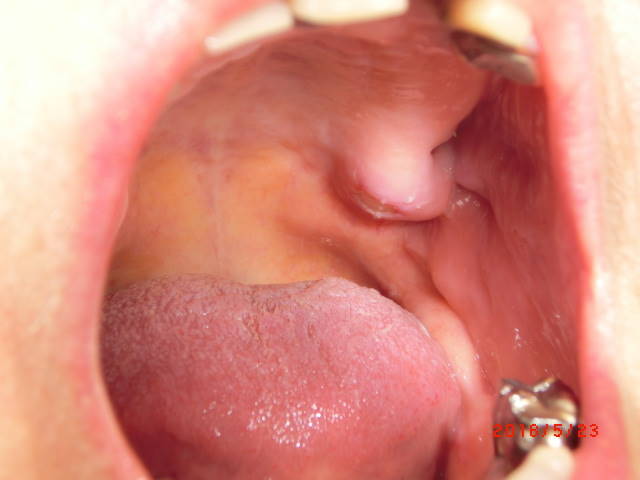

(2)後臼歯隆起部の外骨症

とがった骨の鋭縁に入れ歯が当たって長期間痛みが続いていました。

鋭縁分の骨を削って平にしたら、痛みは完全に無くなりました。

局所麻酔で20分ほどの処置でした。

(2)過剰な上顎結節

上顎結節の一部が尖っていて、入れ歯が出し入れの時に痛み、入れ歯も安定しませんでした。

骨の鋭縁分を削って義歯も安定し、痛みも無くなりました。